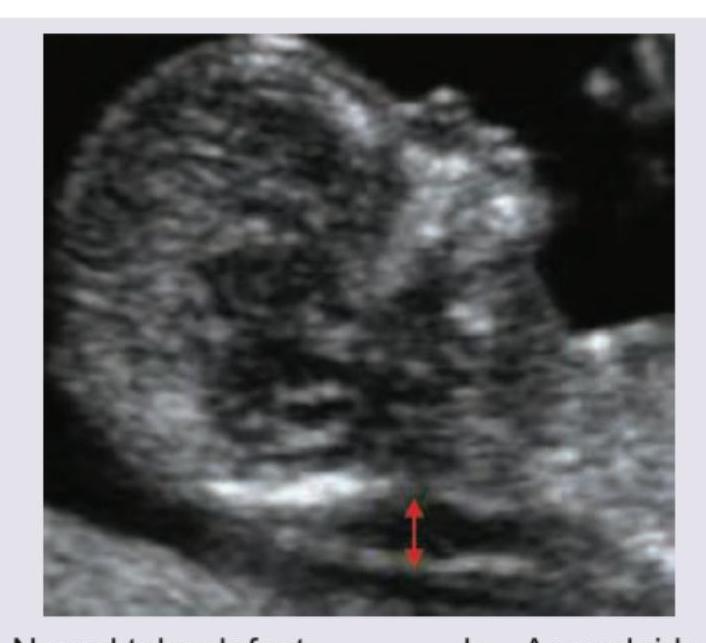

The following USG scan should prompt you to screen for which of the following disorders?

Explanation: ***Aneuploidy*** - The ultrasound image shows increased nuchal translucency (indicated by the red arrow), which is a key marker for **chromosomal abnormalities** like Down syndrome (Trisomy 21). - Increased nuchal translucency combined with other features like **absent nasal bone** (not clearly visible in this image but often associated) warrants further screening for aneuploidy. *Neural tube defect* - Neural tube defects are characterized by abnormalities of the brain and spine, such as **anencephaly** or **spina bifida**, which are not directly indicated by increased nuchal translucency. - While some chromosomal abnormalities can be associated with neural tube defects, nuchal translucency specifically points more strongly to aneuploidy. *Achondroplasia* - Achondroplasia is a form of **dwarfism** recognized by disproportionately short limbs and macrocephaly, which are typically identified later in pregnancy during detailed anatomical surveys. - Increased nuchal translucency is not a primary screening marker for achondroplasia. *Artifact on routine scans* - While artifacts can occur, increased nuchal translucency is a well-established and **clinically significant finding** that requires specific measurements and interpretation in screening for fetal abnormalities. - This measurement is a standard part of the **first-trimester screening** for chromosomal disorders.